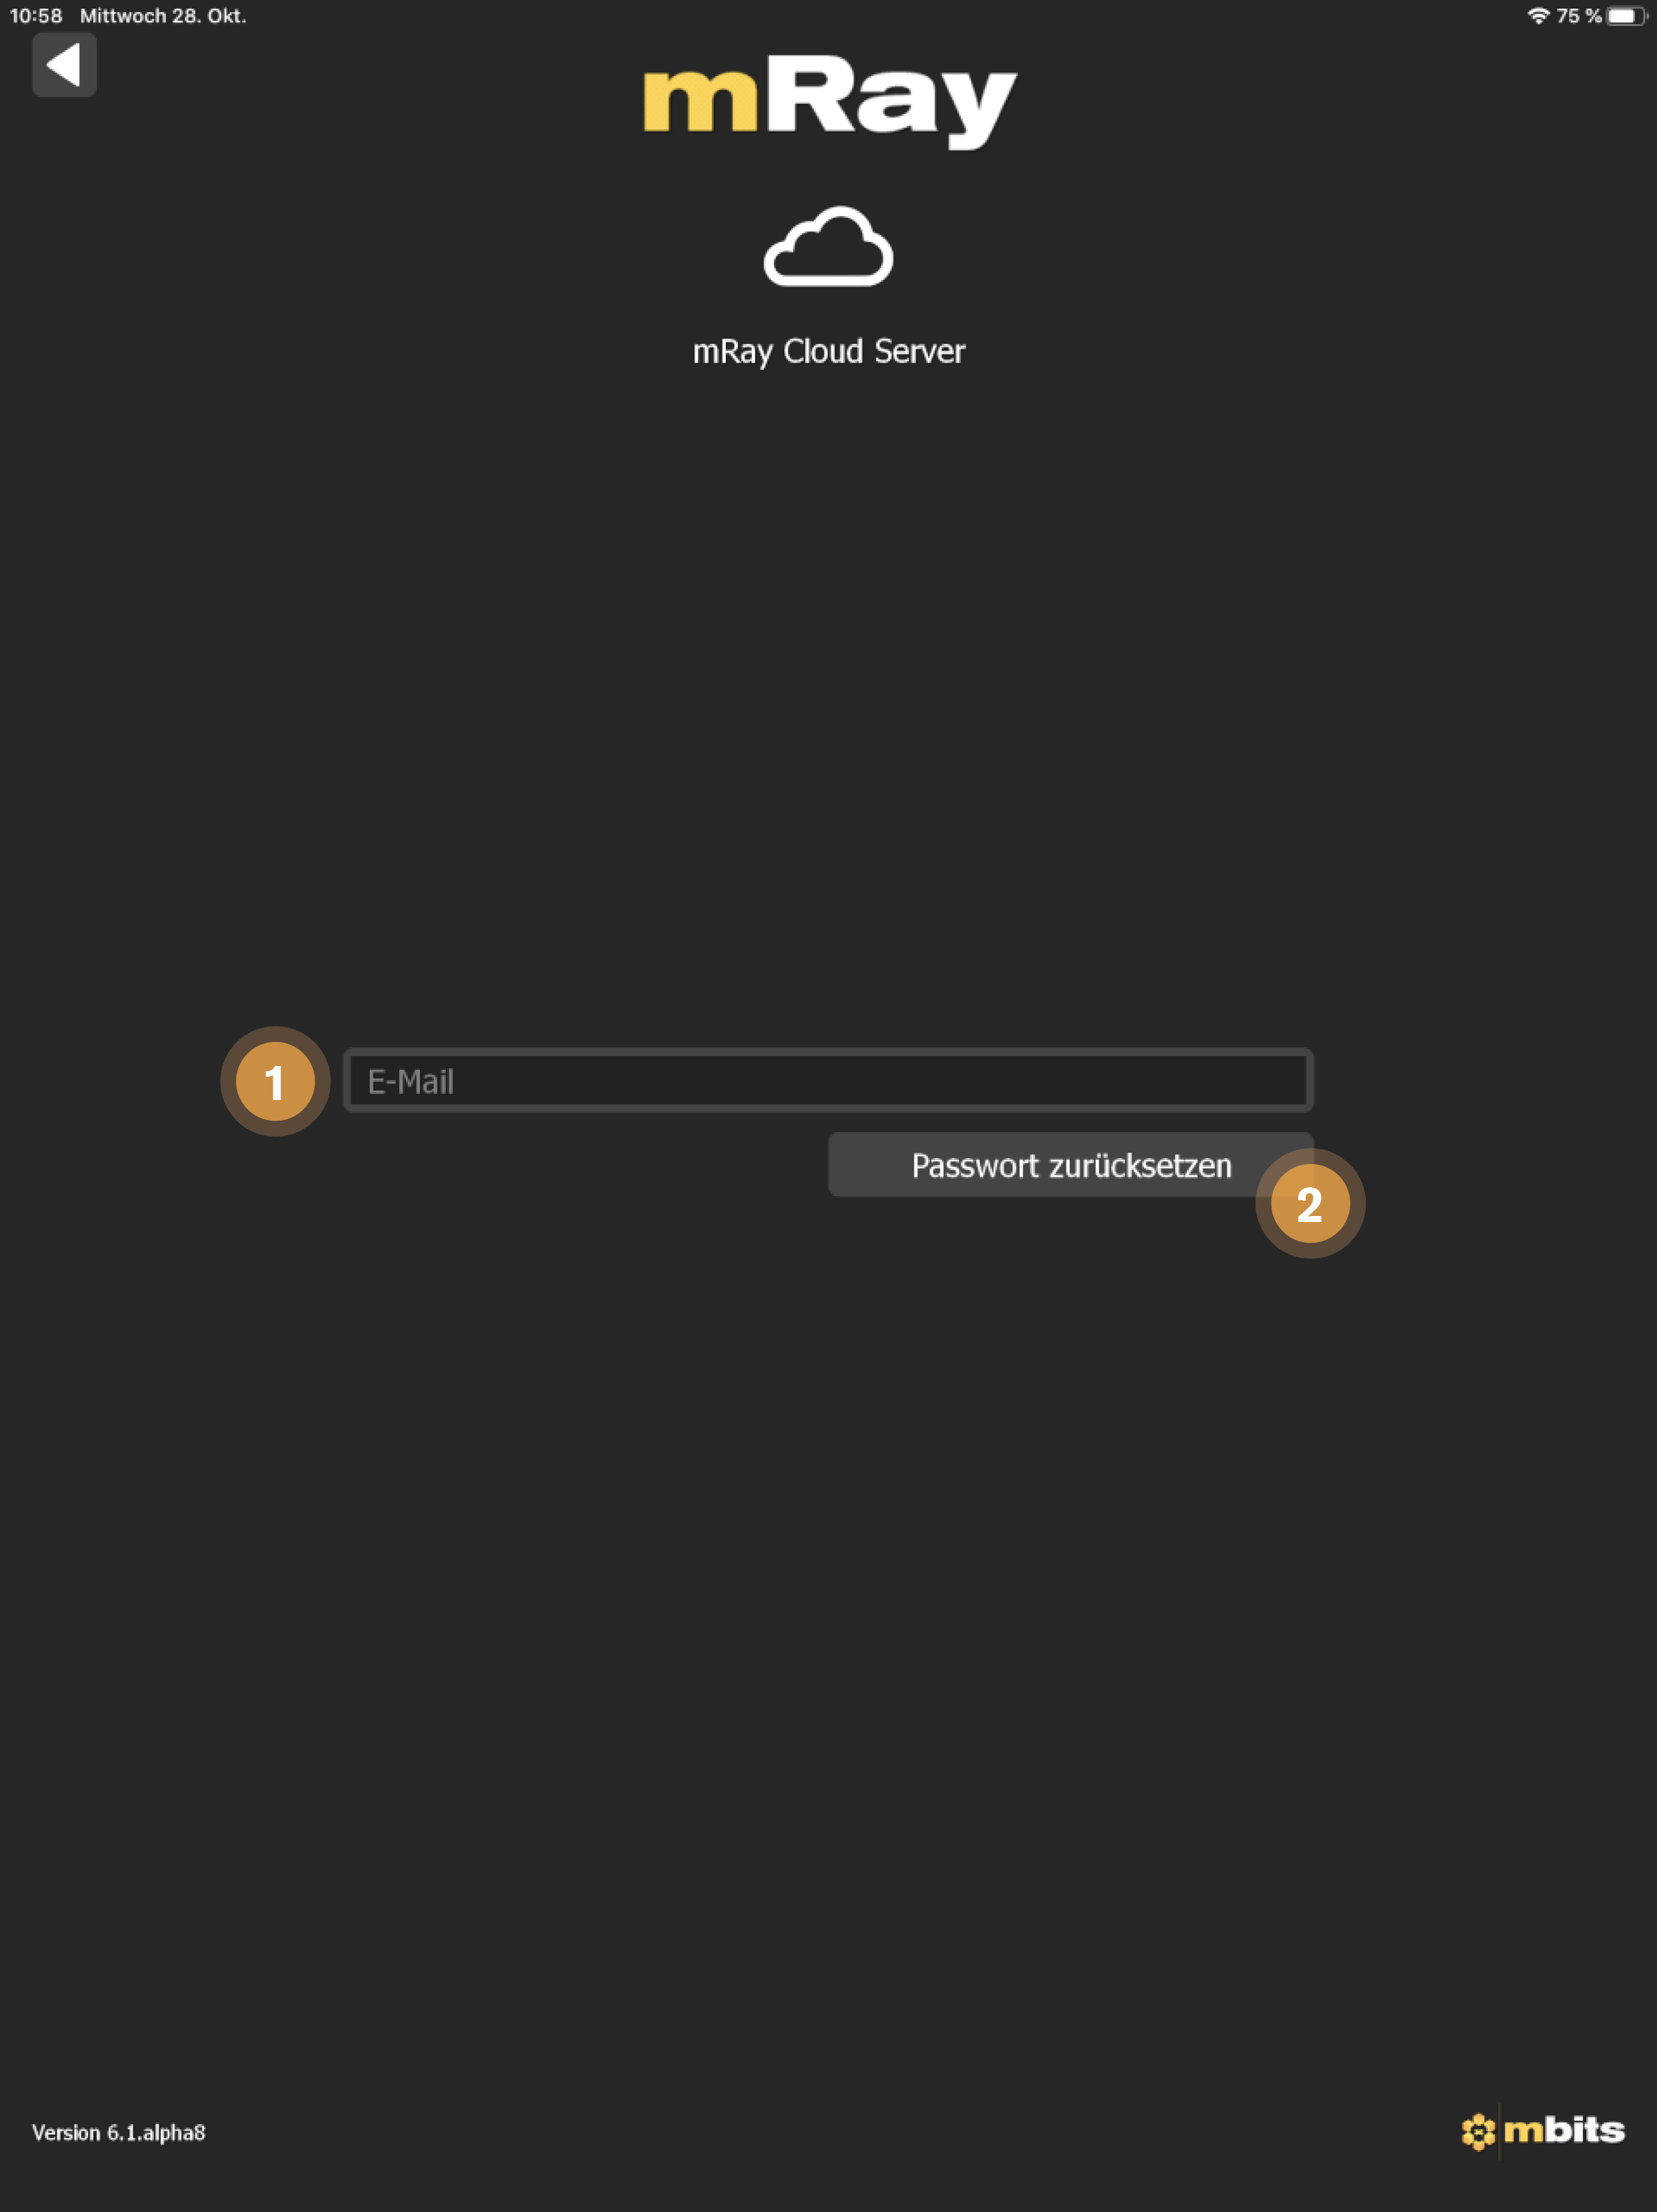

8.2. Cloud Login

Nutzen Sie den mRay Cloud Service um eigene medizinische Bilddaten schnell und einfach hochzuladen.

-

E-Mail: Geben Sie die E-Mail Adresse an, die Sie zum registrieren bei der mRay Cloud verwendet haben.

-

Passwort: Geben Sie das Passwort ein, welches Sie bei der Registrierung für die mRay Cloud angegeben haben.

-

Login: Loggen Sie sich mit den angegebenen Nutzerdaten ein.

-

Jetzt registrieren: Erstellen Sie einen neuen Account für die mRay Cloud. Siehe Cloud Registrierung.

-

Passwort zurücksetzen: Setzen Sie ihr Passwort zurück. Siehe Passwort zurücksetzen.

E-Mail: Die Mailadresse des registrierten Benutzers.

-

Passwort zurücksetzen: Sendet einen Link zum Zurücksetzen des Passworts an die angegebene Mailadresse.